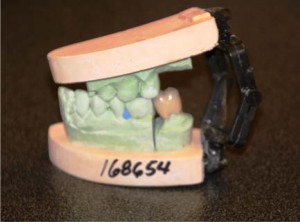

Crown as it is delivered from our lab.